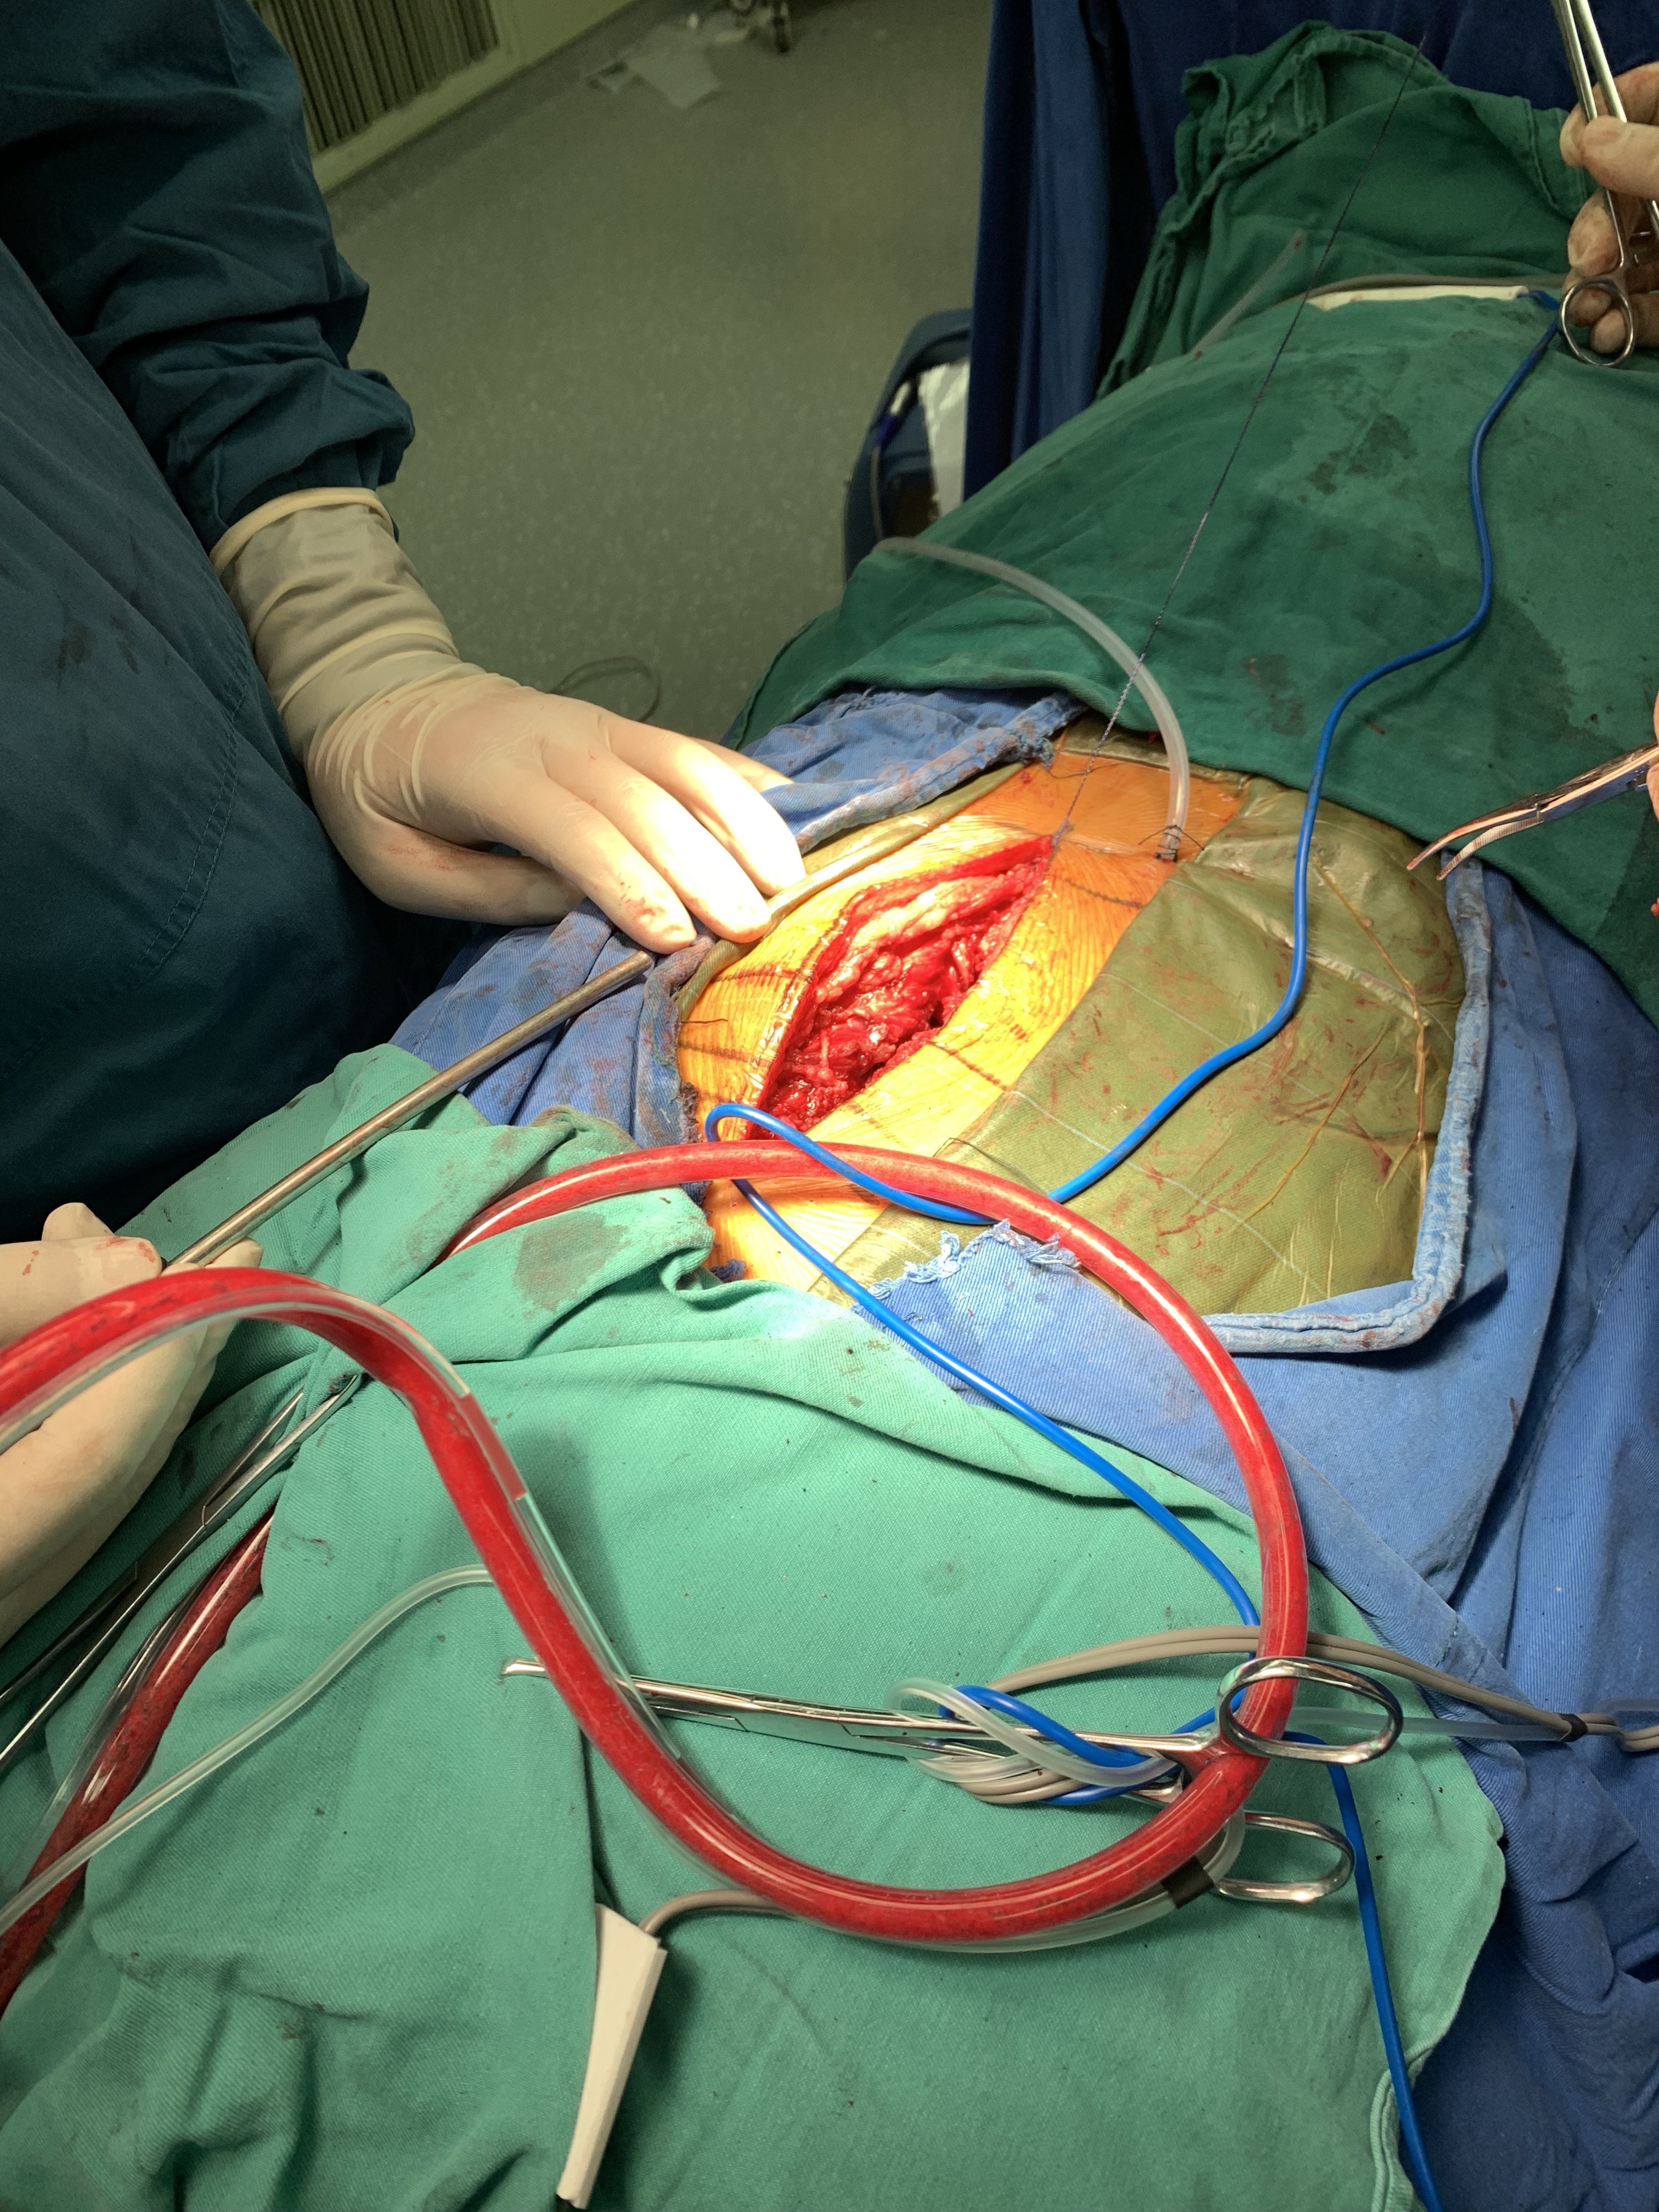

有限切口完成彻底减压

辅助有限椎弓根螺钉固定。